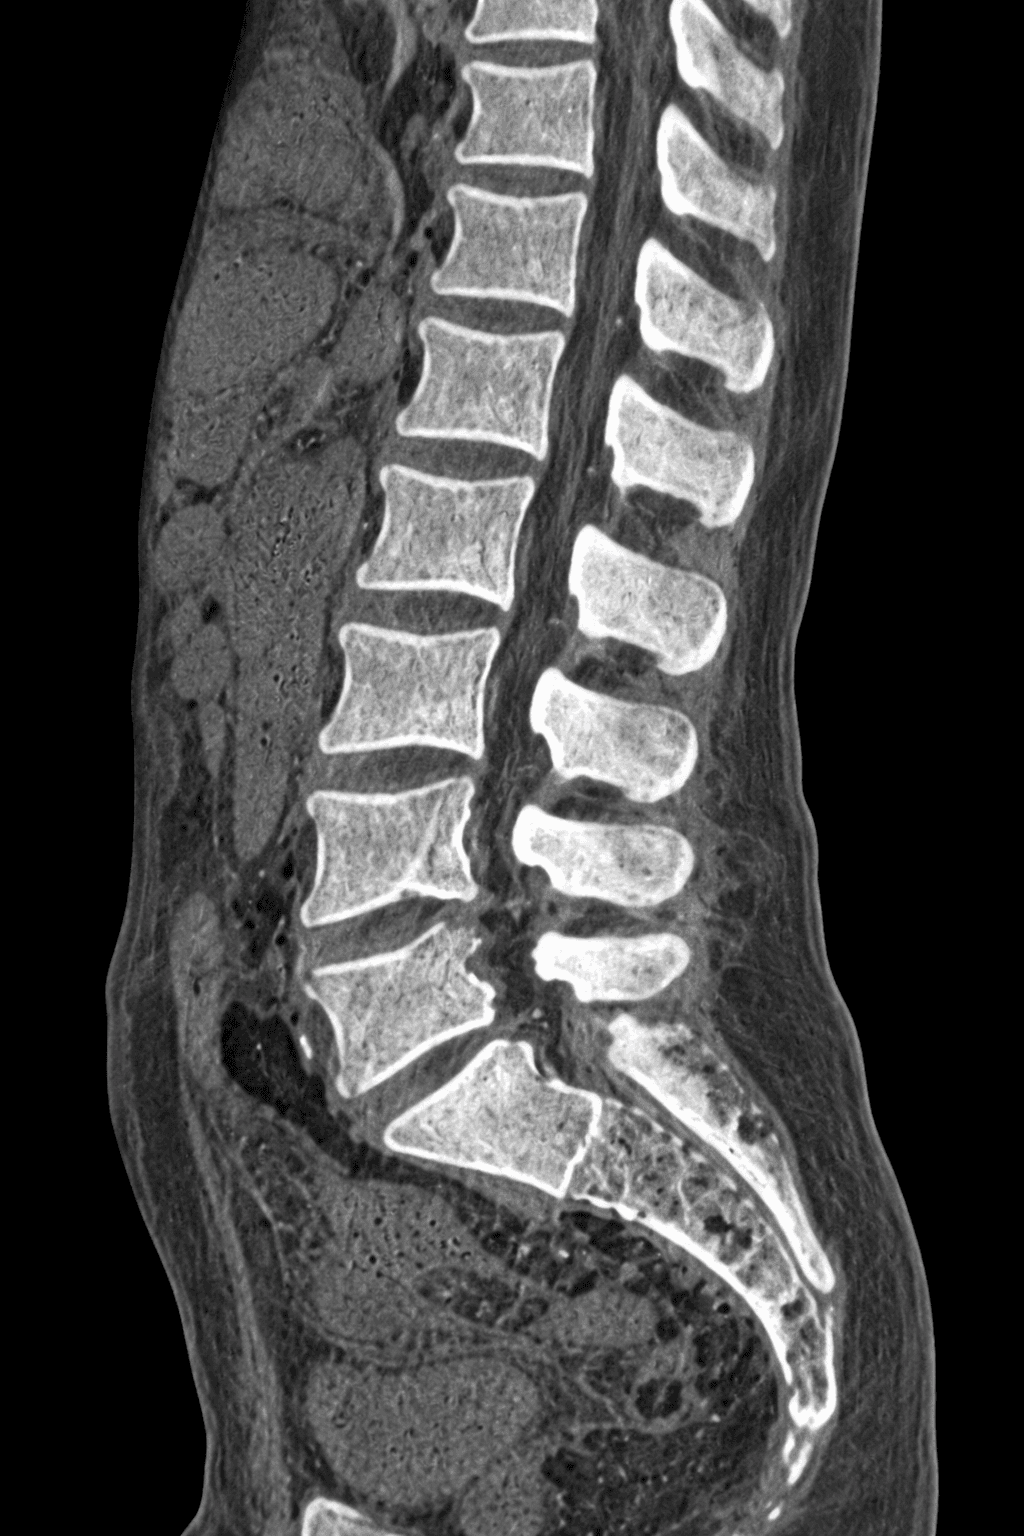

Discover the cause of your back pain with a Lumbar CT scan. We are a medical imaging center with advanced CT scanning technology and expert radiology services for reliable results.